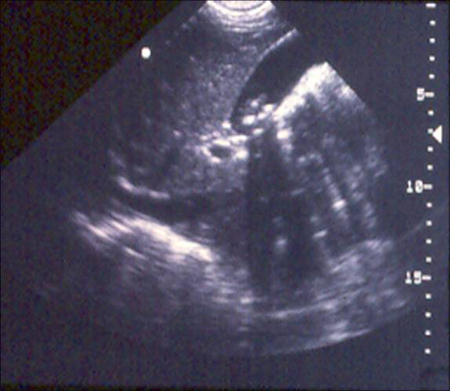

Ultrassonografia de vesícula biliar demonstrando colelitíase com sombreamento característico

Cortesia de Kuojen Tsao; usado com permissão